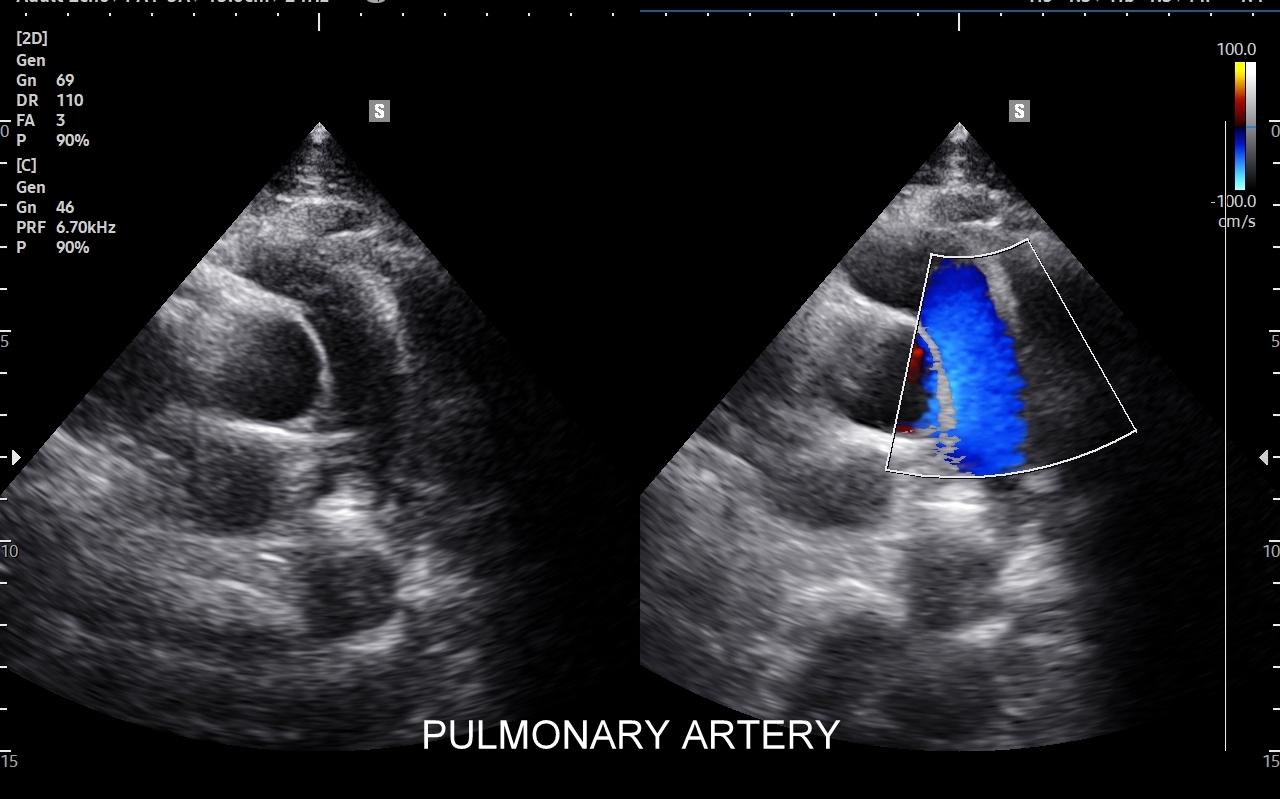

Badanie USG płuc w wybranych przypadkach korzystnie jest połączyć z jednoczesną oceną echokardiograficzną serca oraz dużych naczyń klatki piersiowej, tj. aorty wstępującej i tętnic płucnych. USG układu mięśniowo-szkieletowego klatki piersiowej wykorzystywane jest z kolei w diagnostyce stanów urazowych, takich jak złamanie żeber, czy przeciążenie połączeń chrzęstno-kostnych żeber; w wymienionych przypadkach USG ma wyższą czułość w porównaniu do oceny rentgenowskiej.

Kluczem do wartościowego zastosowania metody USG w diagnostyce pulmonologicznej jest zrozumienie jej możliwości oraz ograniczeń. USG jest niezwykle czułym badaniem w diagnostyce zapaleń płuc zarówno płatowych, jak i atypowych, np. wywołanych przez Mycoplasma lub Chlamydia. W przypadku zapalenia płuc pojawienie się widocznych zmian sonograficznych wyprzedza wystąpienie fenomenów osłuchowych wykrywanych przy osłuchiwaniu klasycznym stetoskopem. Metoda USG jest również bardzo czuła w diagnostyce chorób opłucnej i jam opłucnowych, takich jak nowotwory opłucnej, odma odma opłucnowa czy płyn w jamie opłucnowej. W rękach doświadczonego lekarza badanie USG może być przydatne w wykryciu zatorowości płucnej, a nawet guzów nowotworowych płuc.